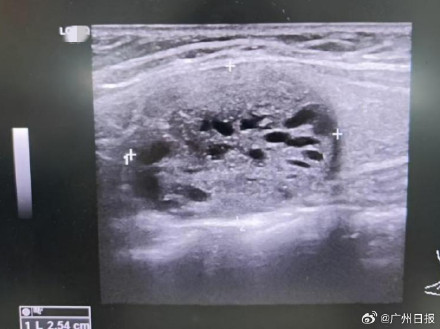

随后的一系列检查,终于揭开了“轻轻一推就骨折”的真相:瑞瑞的血甲状旁腺激素水平飙到501.2ng/L,是正常值(18.5-88.0ng/L)的近6倍;甲状腺超声更显示,他左侧甲状腺下极背侧有个实性占位(大概率是甲状旁腺来源的肿瘤)。

甲状旁腺肿瘤会引发原发性甲状旁腺功能亢进症,过量的甲状旁腺激素会打乱身体钙磷代谢,导致血钙升高、骨质密度降低,让骨骼变得“脆弱不堪”,所以妹妹那轻轻一推,才会让原本该结实的股骨轻易骨折。最终,医院为瑞瑞实施“甲状旁腺肿瘤切除术”。(浙大儿院)